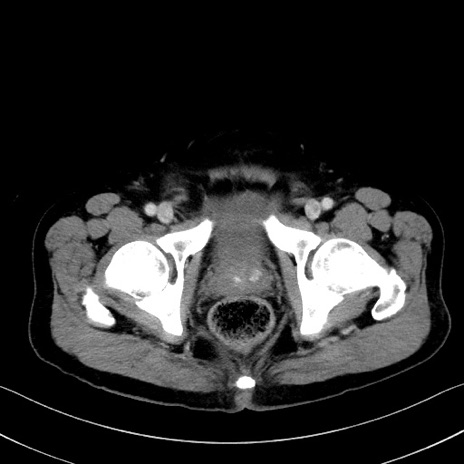

症例35(横断像)

冠状断像

【症例】70歳代 男性

【主訴】腹部膨満、嘔吐

【現病歴】昨日より腹部膨満感出現。本日増悪し、仙痛出現。嘔吐あり、受診。

【既往歴】糖尿病、胆摘後

【身体所見】BP 149/80mmHg、HR 74/min、BT 35.9℃、腹部:膨満、軟、圧痛なし。腸雑音減弱あり。上腹部正中切開瘢痕あり。

【データ】WBC 13500、CRP 1.72